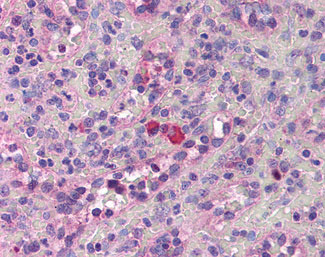

Anti-Thrombopoietin antibody IHC of human spleen. |